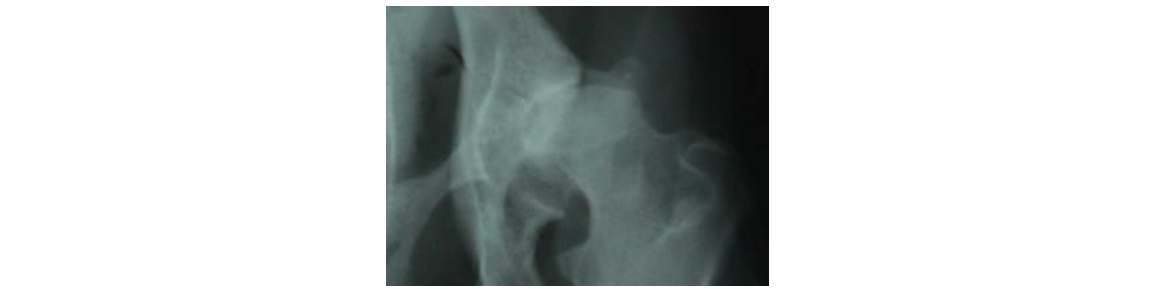

Diagnóstico radiológico. O estudo radiológico é atualmente o

único meio de diagnosticar a displasia coxofemoral. No Pastor

alemão, por exemplo a fiabilidade de deteção por radiografia é

de 16% aos 6 meses de idade, 70% ao ano de idade, 82% aos 18

meses de idade e 95% aos 2 anos de idade. A radiografia oficial

deve ser feita aos 18 meses (nunca em fêmeas em cio). A técnica

radiológica standard, aceite universalmente, requer a sedação ou

anestesia do animal, colocando o animal em decúbito dorsal com

os posteriores distendidos, paralelos e submetidos a rotação

interna, de modo que as rótulas se situem sobre a tróclea do

fémur, evitando a rotação das pélvis. A simetria deve ser

perfeita.

A classificação dos graus de displasia varia segundo os países.

A classificação aceite no nosso país, é a proposta pela

Federação Cinológica Internacional (FCI):

Nenhum sinal de displasia - Grau A

Forma de transição - Grau B

Displasia Leve - Grau C

Displasia Moderada - Grau D

Displasia Grave - Grau E

Com a finalidade de realizarmos a leitura correta da

radiografia recorremos a medidas coxo métricas.

A rotação no caso acima descrito foi de 30 º, a radiografia foi efetuada após a cirurgia. Podemos verificar a introdução total da cabeça femoral no acetábulo no pós-cirúrgico. DARTROPLASTIA. É a cirurgia mais recente que utilizamos para corrigir a displasia em animais que já passaram os 12 meses de idade e que já não podem realizar uma osteotomia tripla. Contudo não são candidatos a uma cirurgia de prótese da anca ou muito menos a uma artroplastia por excisão. A cirurgia consiste em aumentar o acetábulo com uma técnica bastante eficaz e que mantém a cabeça do fémur estabilizada. Temos vindo a realizar esta técnica, desde há dois anos, conseguindo resultados extraordinários.